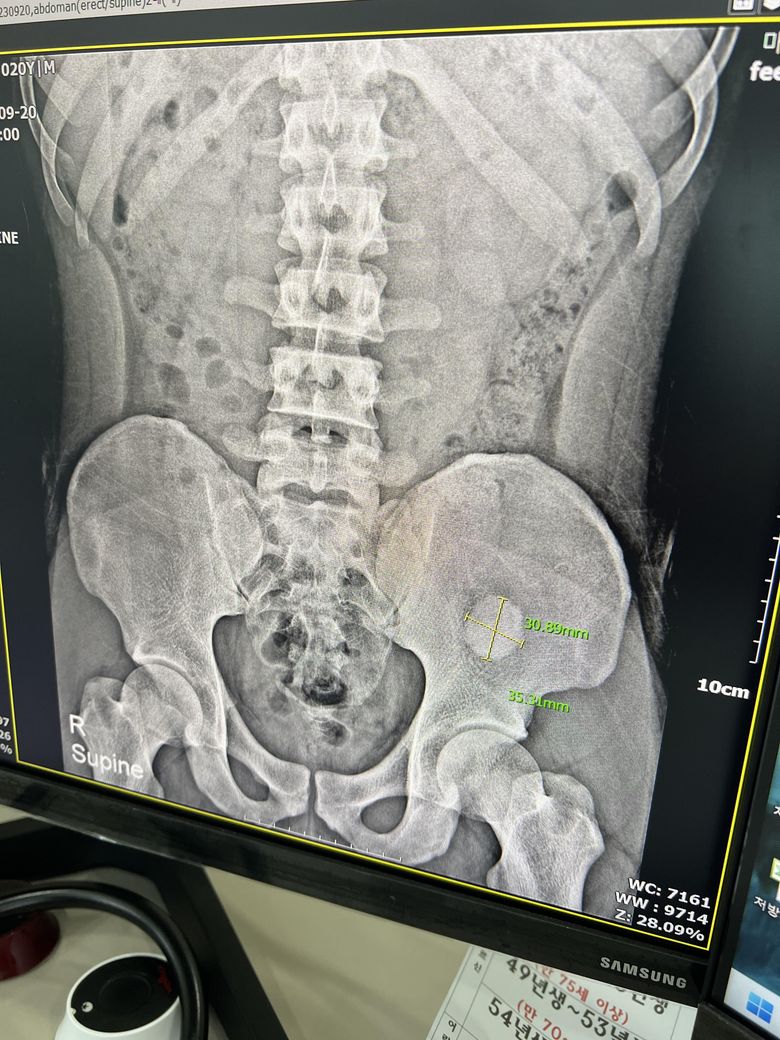

우연히 엑스레이를 찍다 골반에서 뭐가 발견됐습니다

골반 쪽에 동그란 원 형태로 있습니다

아프거나 통증은 없고 우연히 발견했습니다

안녕하세요. 이욱현 의사입니다. 일단은 CT를 찍어야 할 것으로 보입니다. CT가 가능한 곳에서 진료를 받고 검사를 하는 것이 우선이 되겠습니다.

산부인과 쪽으로 난소 혹은 정형외과 쪽으로 근육내에 문제가 있을 가능성이 있습니다.

• 엑스레이 사진을 통해서 구체적으로 무엇인지 알 수 없습니다. 이상 소견이 발견된 만큼 정체가 무엇인지 정밀하게 파악해보아야 하며 CT, MRI 등 더 정밀 검사를 해보아야 할 것으로 사료됩니다.